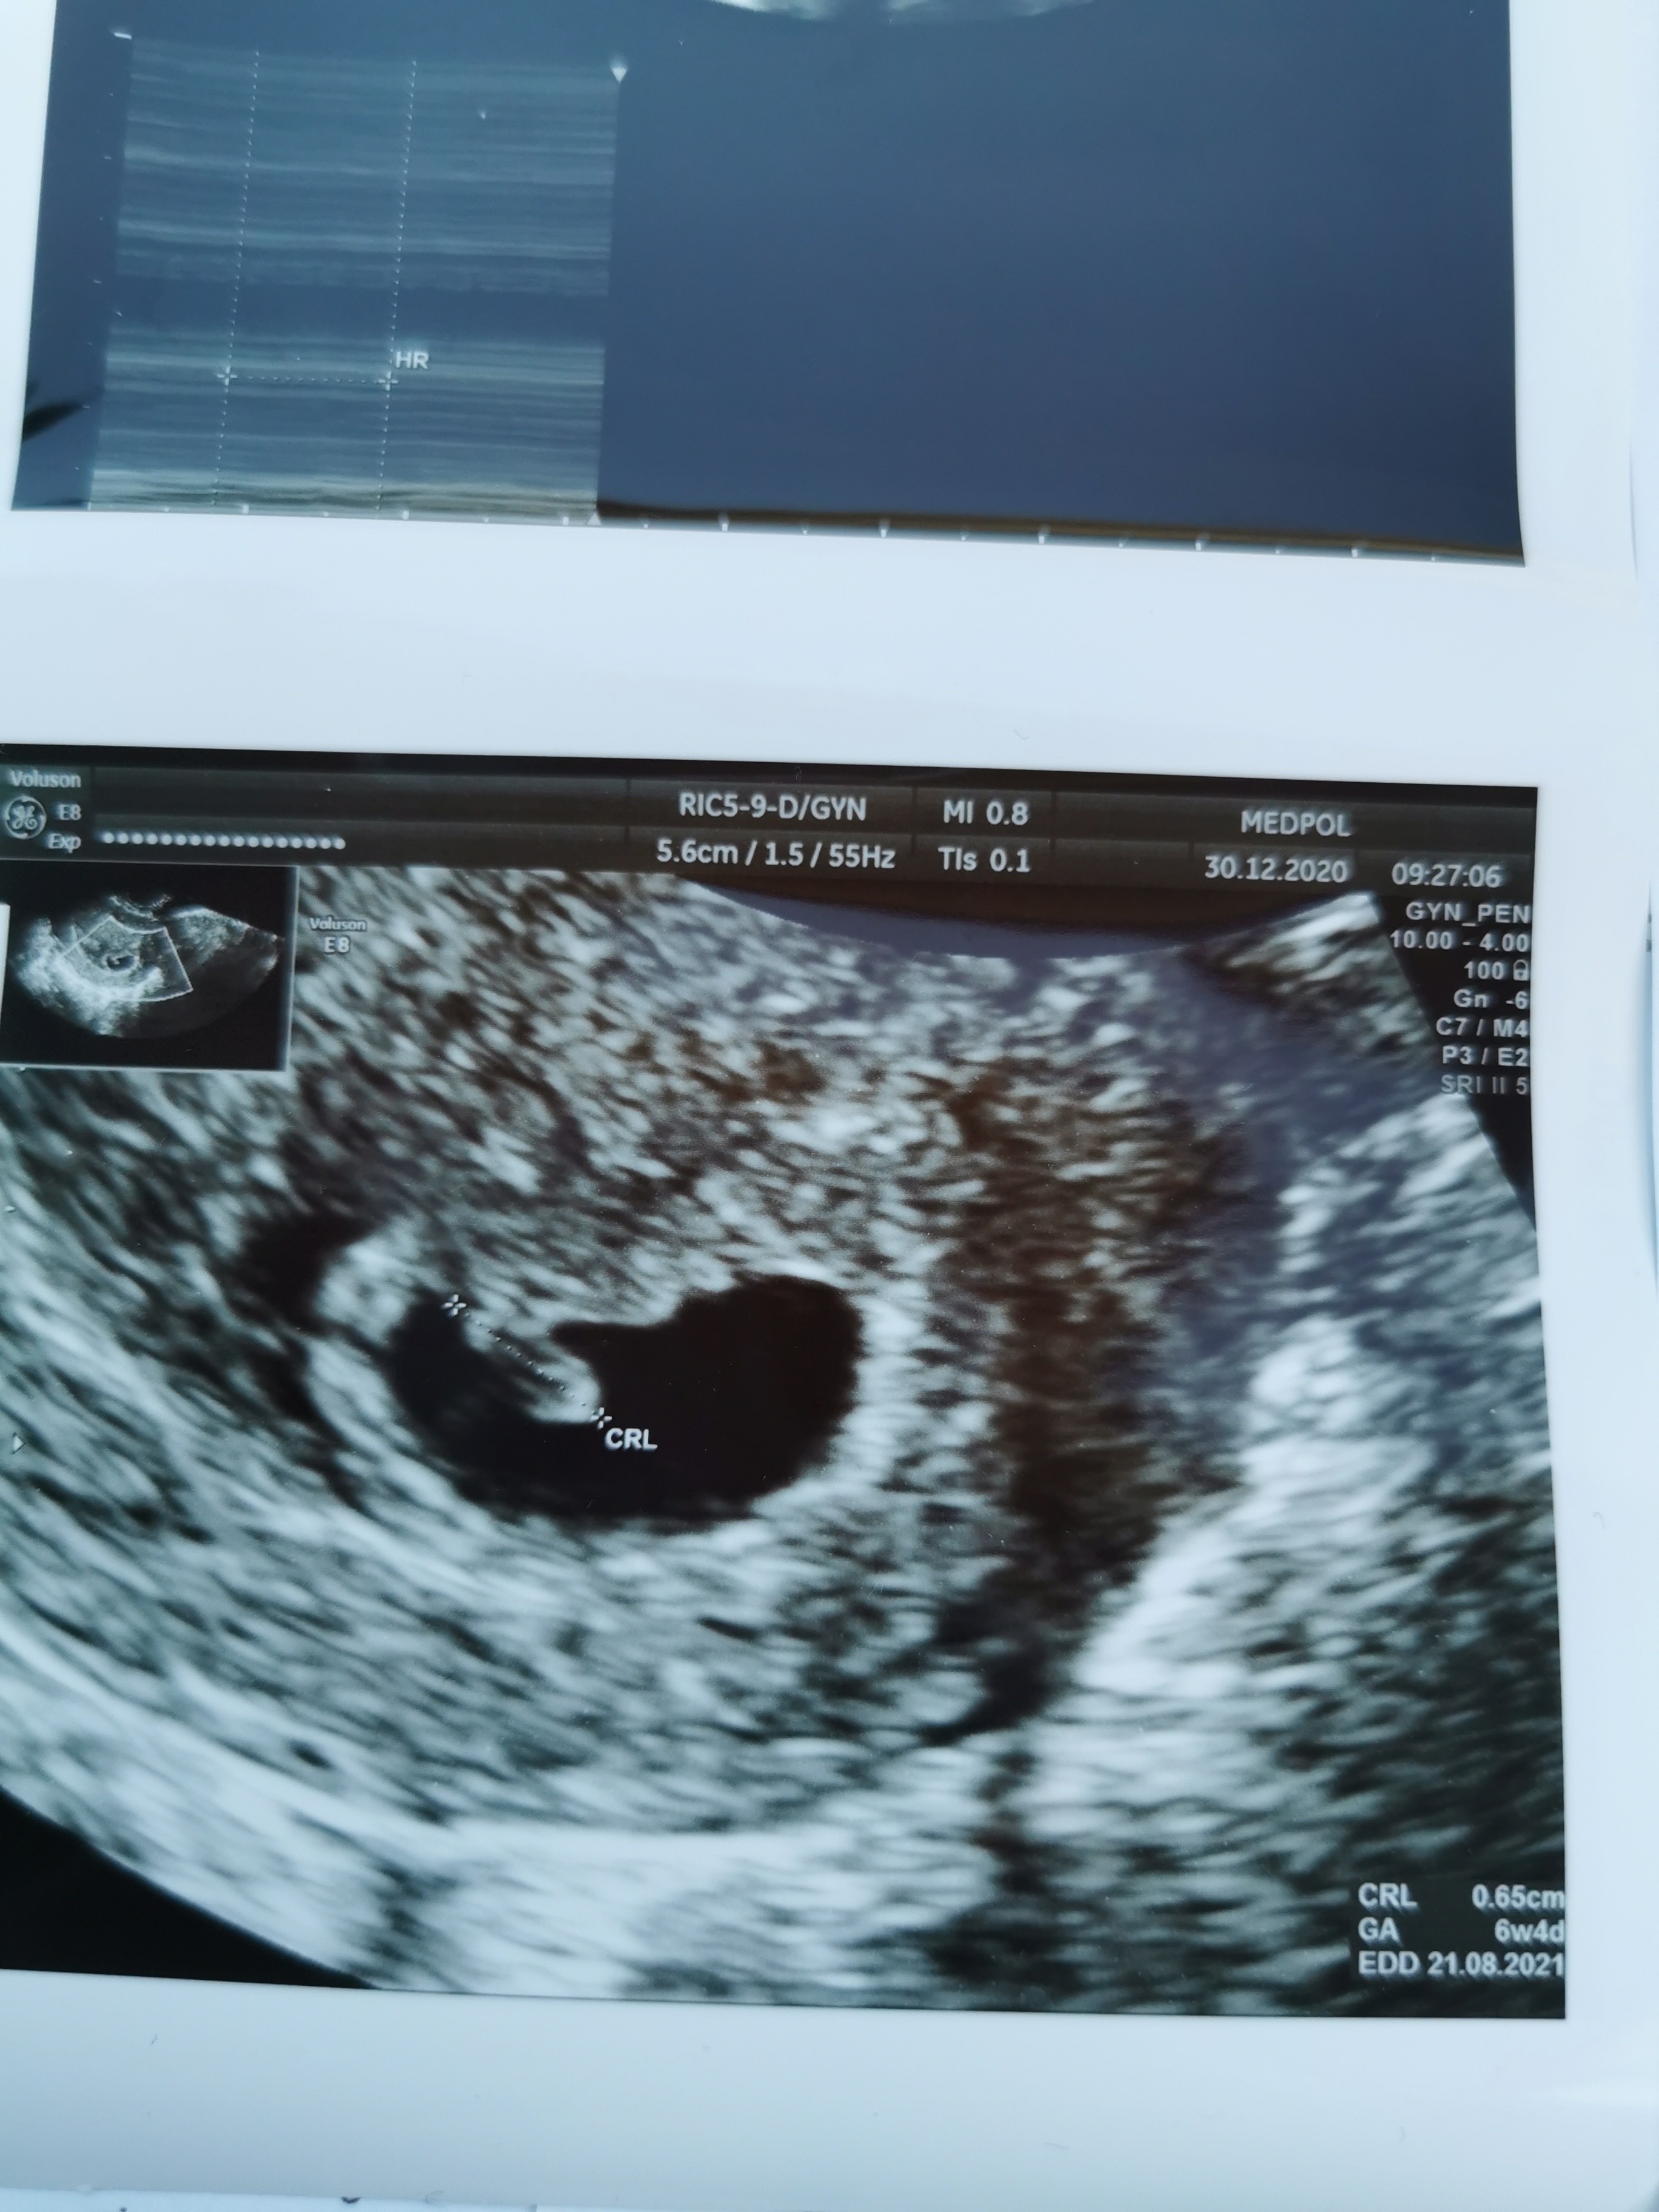

Ja już po wizycie..

Mojemu kropkowi bije serduszko [emoji3590][emoji3590][emoji3590]

Termin z OM 22.08.2021

Termin z USG 21.08.2021 w urodziny mojego..

Więc wszystko jest zgodne z ostatnim terminem @

Zobacz załącznik 1220764

Mojemu kropkowi bije serduszko ❤️❤️❤️